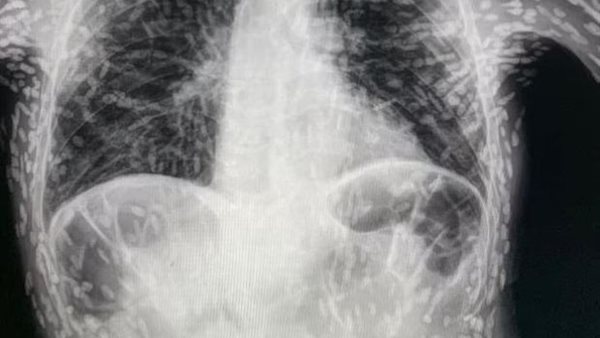

أشعة سينية تكشف حالة صادمة لمريض مصاب بالديدان الشريطية

أصيب رجل بسعال شديد وعند ذهابه إلى المستشفى، فوجئ الأطباء بصور الأشعة السينية؛ حيث وجدوا أن الديدان الشريطية تملأ أنسجة وعضلات الرجل، وذلك وفقًا لذا صن البريطانية.

كشفت الأشعة السينية، التي شاركها طبيب على تويتر، عن مئات النقاط مضيئة التي تشير إلى بقايا متكلسة لطفيلي، وتحدث هذه الحالة المسماة داء الكيسات المذنبة، عندما تدخل يرقات أحد أنواع الدودة الشريطية؛ التي تعيش عادةً في الأمعاء، إلى أنسجة مثل العضلات أو الدماغ.